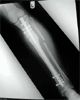

Had a fall and developed varus

deformity over distraction site

Post

Op

Varus deformity over distraction site

Post-op 2nd surgery :

Acute correction with IM nailing